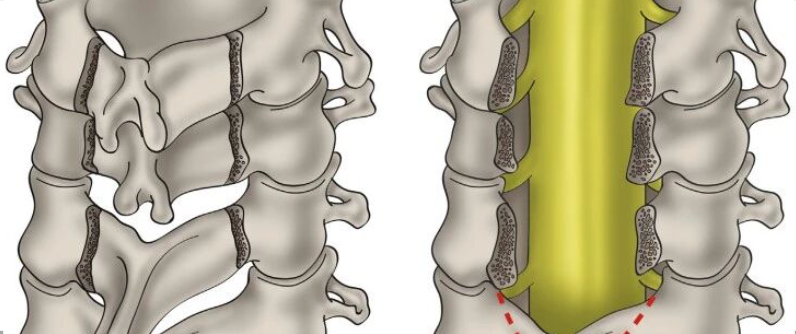

肩关节镜技术

117分钟

5.5万人学习